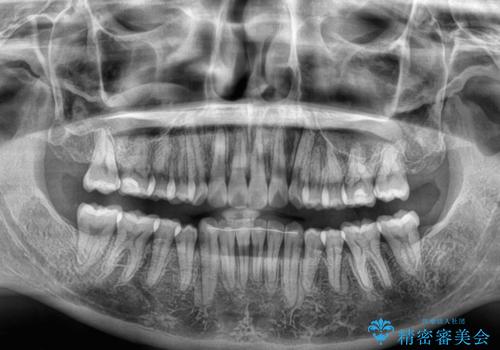

- 前歯のデコボコを治したいとのことで来院された患者様です。

上下顎ともに歯列全体の後方移動とIPR(歯と歯の間を削る)によってデコボコが解消するように設計し、インビザラインにより治療を行うこととしました。